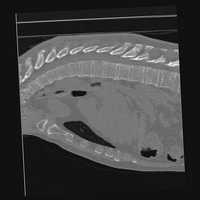

Exp. 3: Adult thorax data: To show the versatility of our approach we also apply it to adult thorax scans. For this experiment no organ specific training is performed but the whole volume is used. We evaluate reconstruction performance similar to Exp. 1 and Ti^^subscript𝑇𝑖\hat{T_{i}} prediction performance when ΩΩ\Omega is projected on an external plane, comparable to X-Ray examination using C-Arms. The latter provides insights about our method’s performance when applied to interventional settings in contrast to motion compensation problems. 60 healthy adult thorax scans were randomly selected, 51 scans used for ΩtrainsubscriptΩ𝑡𝑟𝑎𝑖𝑛\Omega_{train} and nine scans used for ΩvalidationsubscriptΩ𝑣𝑎𝑙𝑖𝑑𝑎𝑡𝑖𝑜𝑛\Omega_{validation}. Each scan is intensity normalised and resampled in a volume of 200×200×200200200200200\times 200\times 200 with spacing 1mm×1mm×1mm1𝑚𝑚1𝑚𝑚1𝑚𝑚1mm\times 1mm\times 1mm. Using the Fibonacci sampling method, 25 sampling plane of size 200×200200200200\times 200, evenly spaced between -50 and +50, were rotated over 500 normals. Training took approximately 20 hours for 60 epochs. Fig. 4c shows an example reconstruction result gaining 28dB PSNR with additional SVR. Ti^^subscript𝑇𝑖\hat{T_{i}} prediction takes approx. 20 ms/slice for this data.

Figure 4: (a): Comparison of a single slice from raw low-dose thorax CT data; (b): reconstruction based on SVRNet Ti^^subscript𝑇𝑖\hat{T_{i}} regression; (c): SVR initialized with SVRNet transformations after four iterations of SVR; (d): PSNR of (b) and (c) compared to (a). (e): shows a projection of an unseen pathological test CT volume as DRR and (e) shows a DRR at the location predicted by our method when presented with the image data in (e).

We replicated the experiment on adult thorax data without specifically segmented organs. This approach was applied to CT acquisition, shown in Fig 13 and 14, as well as Digitally Reconstructed Radiographs generated using Siddon-Jacobs Ray Tracing shown in Fig. 16.